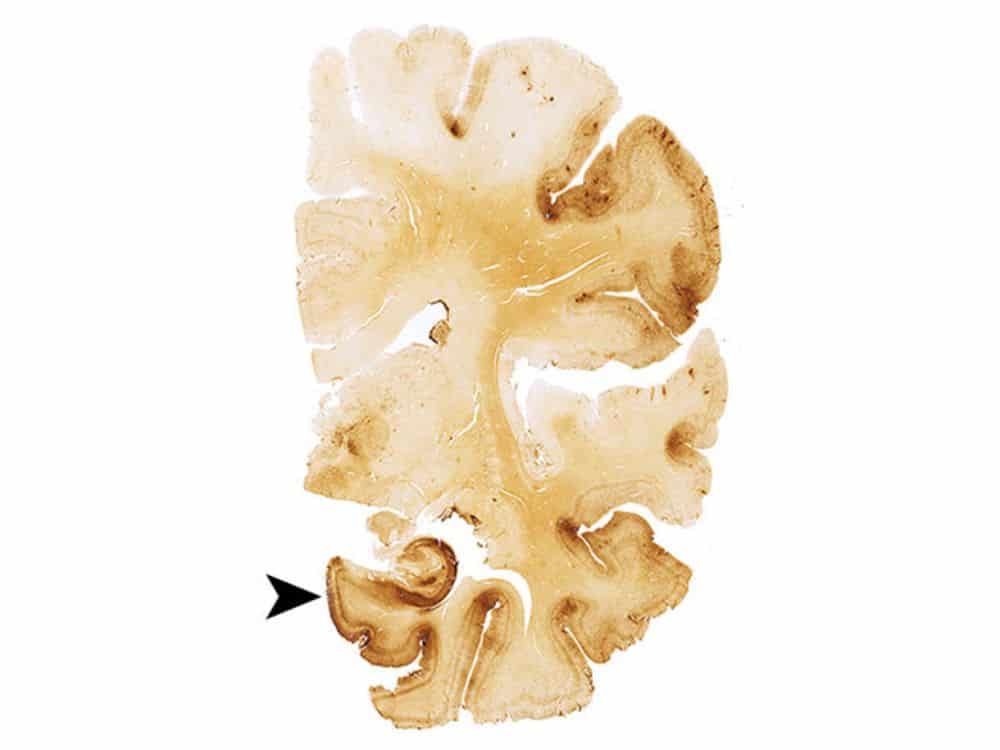

اعتلال الدماغ الرضحي المزمن هو مرض تنكسي (تتراكم آثاره عبر الوقت). وبخلاف ارتجاج الدماغ، الذي ينجم عن ضربة مباشرة على الرأس، فإن اعتلال الدماغ الرضحي المزمن ينجم عن تعرض الرأس لصدمات متكررة لا تؤدي أي منها بمفردها للإصابة بارتجاج في الدماغ. تؤدي تلك الصدمات إلى تراكم بروتين يُدعى تاو tau في الدماغ، يُسبب تموت الخلايا العصبية في أماكن انتشاره.

ومن غير المفاجئ أن ترتبط شدة العلامات بمدة ممارسة اللعبة، فقد أظهر لاعبو المدارس الثانوية العلامات الأقل لتراكم بروتين تاو في الدماغ، يليهم لاعبو الجامعات، وأخيراً اللاعبون المحترفون في الدوري الأميركي، الذين أظهروا العلامات الأكبر لتراكم بروتين تاو في الدماغ.

مصدر الصورة: مجلة الجمعية الأميركية للطب/ماكي وزملاؤه.